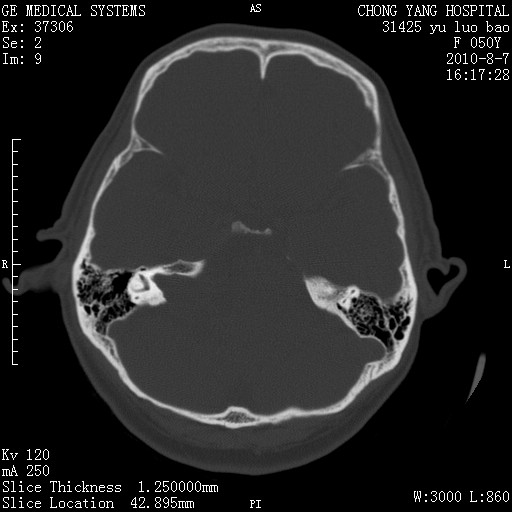

骨窗示右侧内听道扩大,考虑右侧听神经瘤。

右侧桥小脑角去等密度占位,右侧内听道扩大、骨质吸收,考虑:右侧听神经瘤,建议增强检查。

右侧桥小脑角区等密度占位,内耳道扩大,听神经瘤